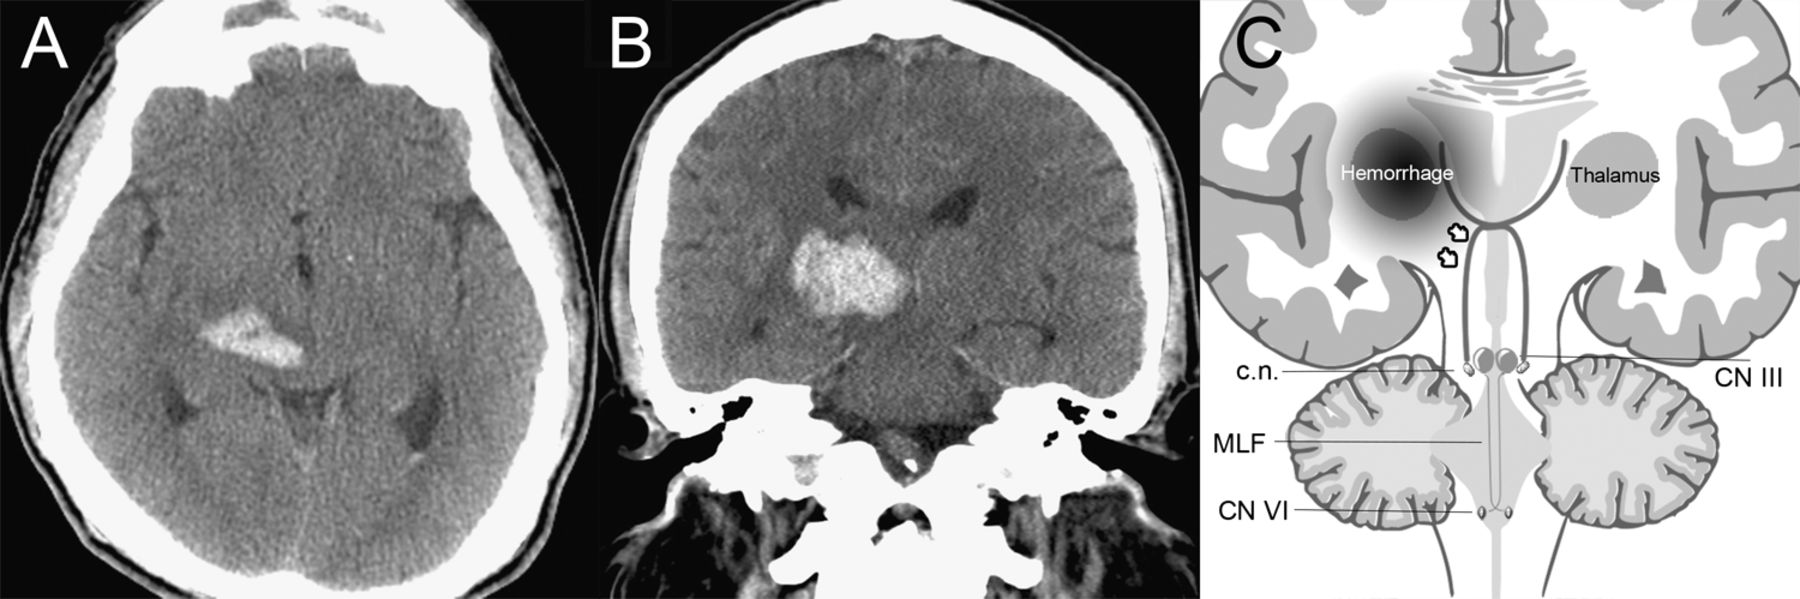

图1

轴向与结构说明和冠状CT显示丘脑血肿对收敛的影响系统

(A, B)对丘脑出血与中脑扩展和2毫米第三脑室中线的转变。(C)收敛性神经元(花旗集团(c.n:行情)眼球运动的核背外侧,由下行控制在丘脑皮层通路交叉的区域。单侧丘脑病变同侧和交叉成十字形侧纤维破坏(箭头),导致与对侧突出眼睛的双边收敛过剩。MLF =内侧纵束。

收敛过度很少是由丘脑病变引起的。1收敛性神经元,眼球运动的核背外侧,由下行控制皮质通路。2丘脑下的地区的通路交叉成十字形,单侧丘脑病变可能会扰乱身体的同侧的和交叉侧纤维(图1 c)。赞同清醒表明其与附近的网状结构。